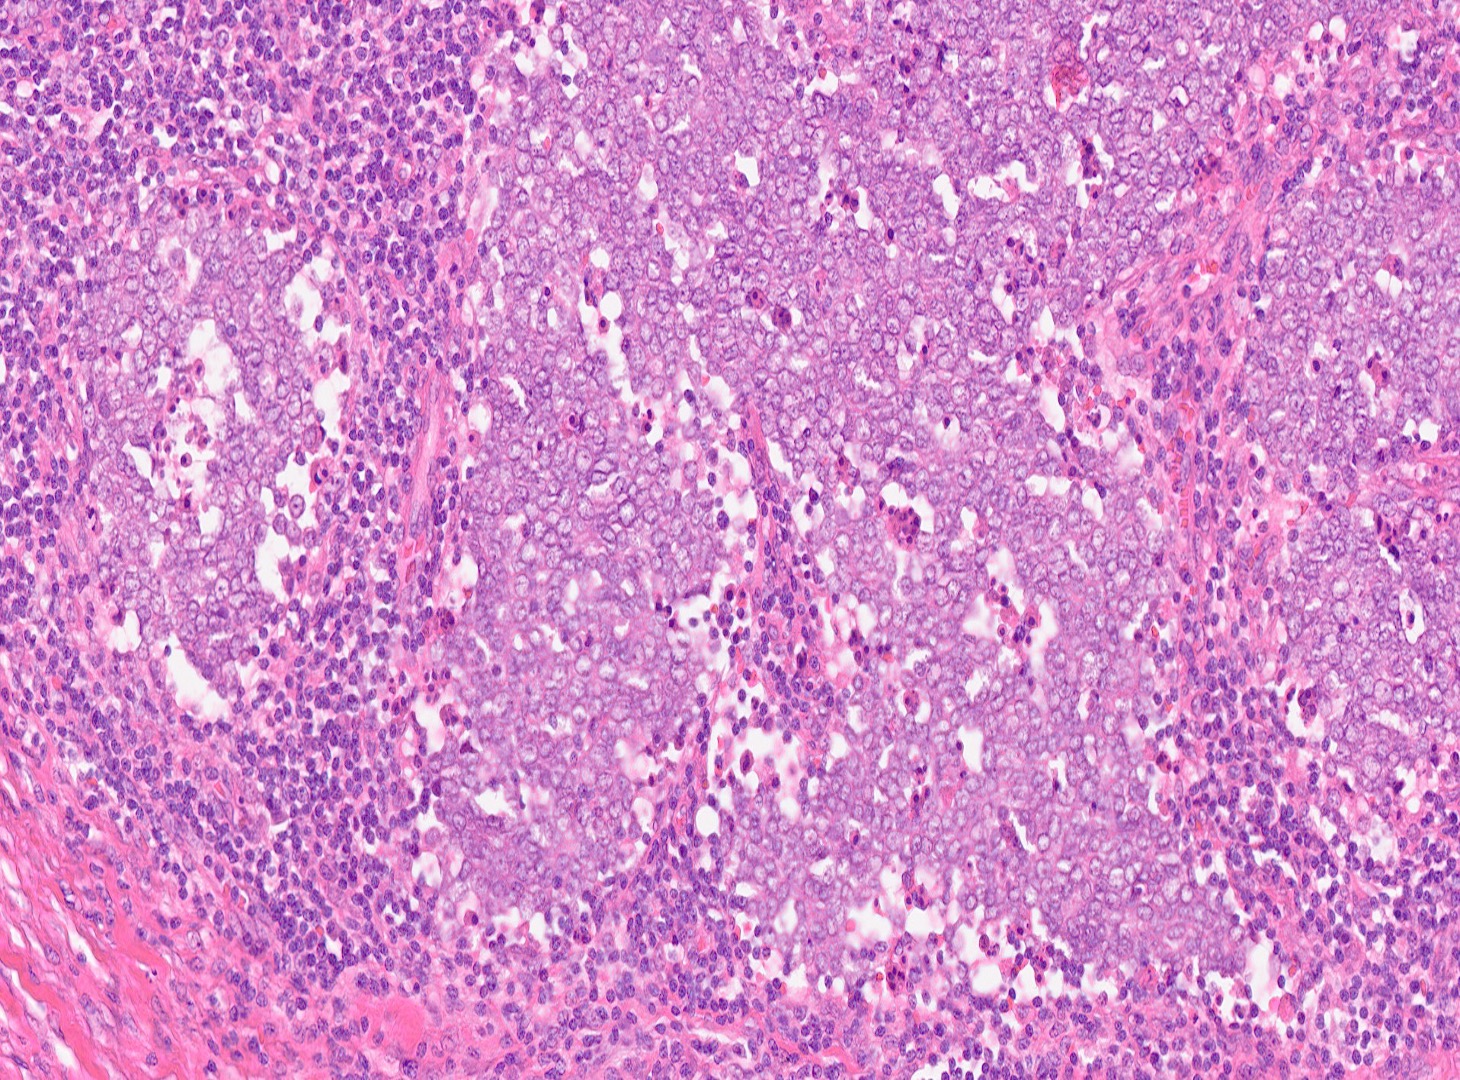

H&Ex20